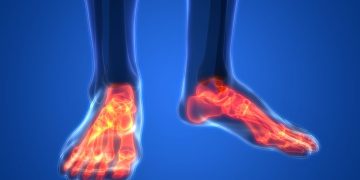

زهافا سي: "عانيت من مشكلة في الغضروف في ركبتي ولم أسير على الإطلاق. قال الأطباء إنه لا يوجد شيء أفعله ، لكن أورن أنقذني!"

عانت زهافا ج من وسط البلاد من آلام شديدة في ركبتيها ولم تستطع المشي. قام الأطباء بتشخيص تآكل الغضروف ولم يتمكنوا من المساعدة. التي وضعتها أخيرًا على قدميها كانت أورن ظريف.

"لقد عانيت من تآكل الغضروف ، قال الأطباء إنه لا علاقة له بذلك ، لكن أورين كان قادرًا على المساعدة … منذ أن بدأت علاجاته ، حتى أنني فقدت وزني كما وعدني أورين وهو موجود. ليس لدي أي كلمات سوى لأقول شكرا ، شكرا لك ، شكرا لك! ".